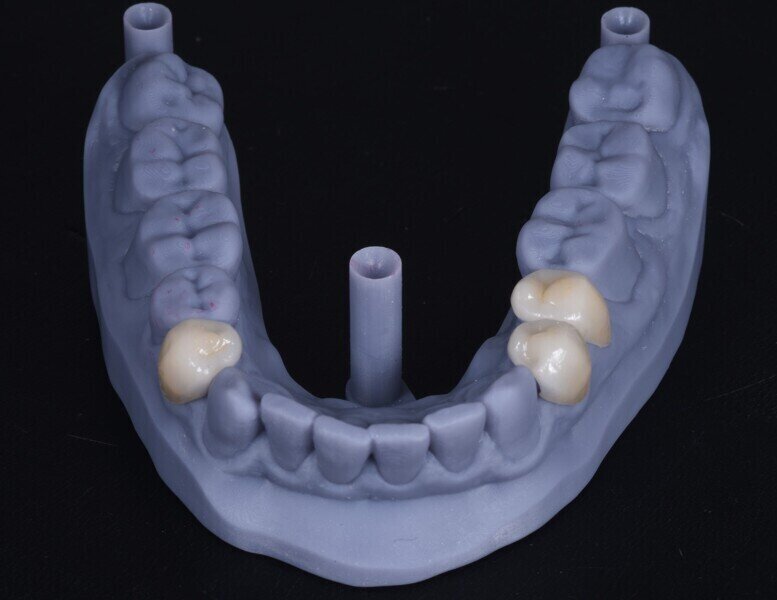

Dostavby byly navrženy v softwaru exocad (obr. 4) a pro jejich výrobu byl zvolen lithium disilikát (obr. 5). Výplně byly adhezivně fixovány v ústech pacienta. Po zvýšení VRO byla incizální okluze pacienta ideální pro rekonstrukci řezákového vedení, pro kterou bylo nutno zajistit pacientovi ortodontickou léčbu (obr. 6). Po ukončení ortodontické léčby byly opotřebené incizální hrany dolních řezáků obnoveny přímou dostavbou kompozitem (obr. 7).

Obr. 4a–f: Návrh laterálních dostaveb v programu exocad.

Obr. 5a, b: Zvýšení vertikálního rozměru okluze.